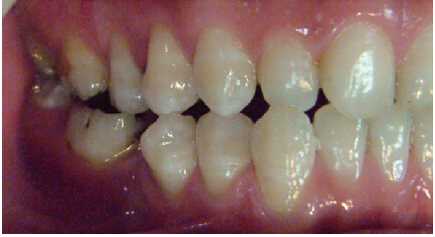

這種咬合接觸的結(jié)果是局部的咬合力集中在凸點(diǎn)接觸的位置,不能被有效分散,可造成受力部位牙體、牙周組織的應(yīng)力集中。最常見的表現(xiàn)是后牙頰舌向呈對(duì)刃關(guān)系,另外還常見于不完全遠(yuǎn)中關(guān)系或不完全近中關(guān)系的情況,此時(shí)從近遠(yuǎn)中方向來看,上下后牙牙尖之間凸凸相對(duì)(圖3)。

圖3 后牙凸凸接觸關(guān)系